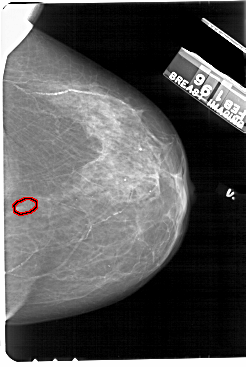

A_1697_1.LEFT_MLO

LEFT_MLO LINES 5491 PIXELS_PER_LINE 3721 BITS_PER_PIXEL 12 RESOLUTION 43.5 NON_OVERLAY